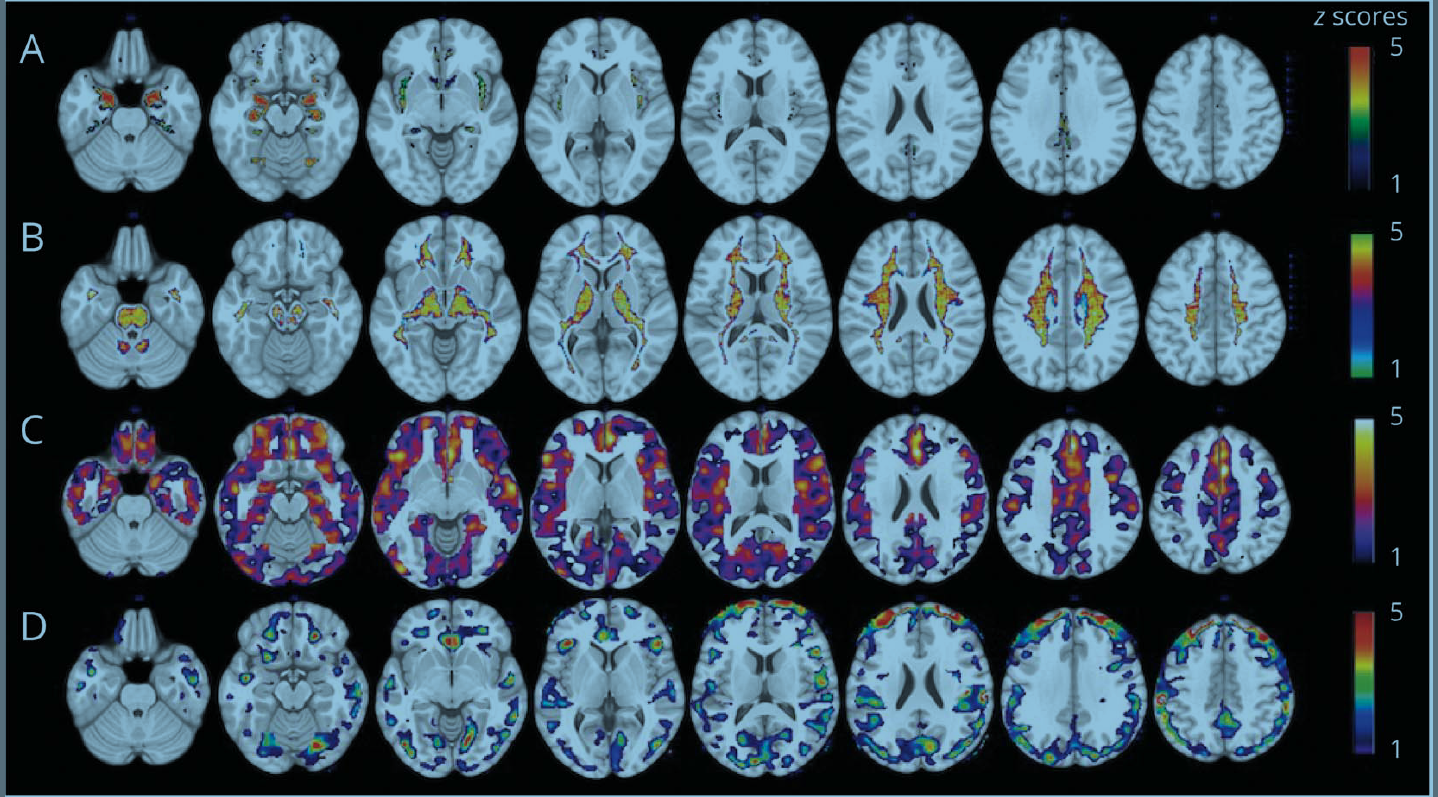

Duke researchers determined task-fMRI does not produce reliable predictions individuals will respond in particular circumstances or future mental health.